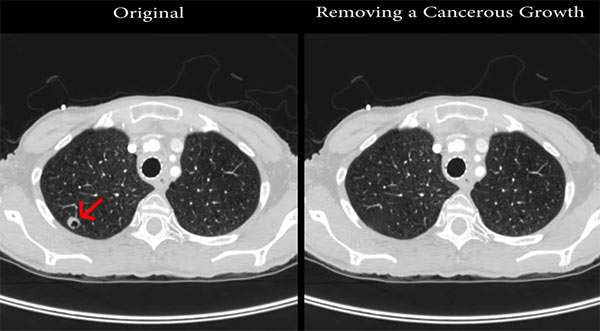

I ricercatori dei Cyber Security Labs della Ben Gurion University hanno dimostrato in che modo, creando un malware capace di alterare i referti degli esami medici. Nella demo sono stati impiegati quelli ottenuti sottoponendo i pazienti a indagini cliniche mediante tomografia computerizzata (CT) e risonanza magnetica (MRI). Il codice è riuscito a manipolare i file generati eliminando dalle immagini dei polmoni (anche quelle 3D) la presenza di cellule tumorali (come visibile nello screenshot qui sotto) oppure aggiungendole dove in realtà assenti.

L’analisi di 70 scansioni così modificate da parte di personale specialistico ha confermato l’efficacia del malware: i medici non sono stati in grado di riconoscere le alterazioni apportate dal software nel 98% dei casi, nemmeno ricorrendo all’impiego di programmi sviluppati appositamente per supportare l’occhio di un esperto durante la diagnosi. Non è dunque difficile comprendere come le potenziali conseguenze di una simile minaccia possano essere disastrose per la salute dei diretti interessati, celando la presenza di un problema oppure creando falsi positivi.